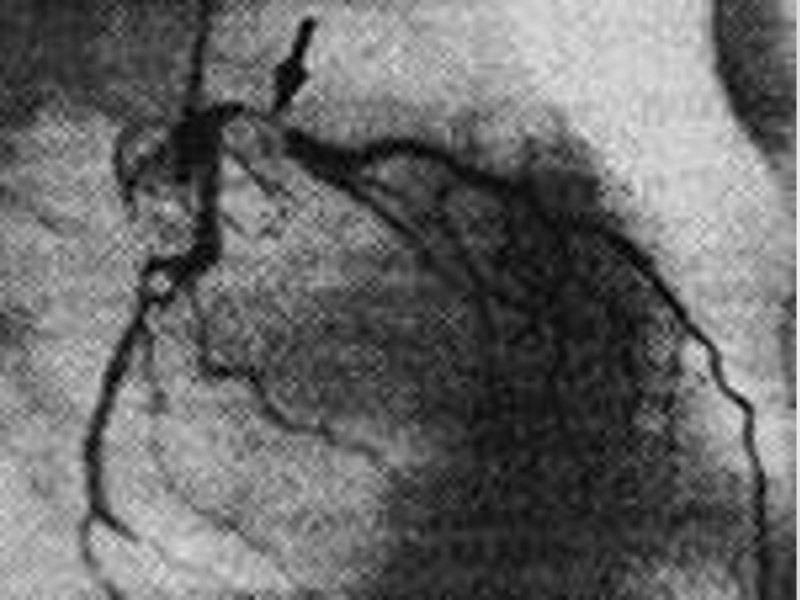

КАГ Коронарография является инвазивной процедурой. Использование ангиографического исследования с диагностической целью должно осуществляться по строгим показаниям, когда другие дополнительные менее травматичные методы исследования не позволили установить точный диагноз. Проведение коронарографии бывает также необходимо при планировании хирургического лечения той или иной сердечнососудистой патологии.

Показания к КАГ Необходимость точного подтверждения заболевания сердца и сосудов (например, ишемическая болезнь сердца, патология клапанов сердца или патология аорты). Произвести оценку функции сердца и миокарда. Определить показания и вид предполагаемого хирургического лечения (например, это будет эндоваскулярное вмешательство или шунтирующая операция).